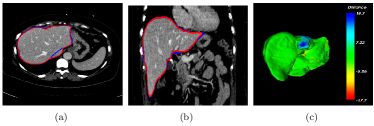

Refer to caption

Figure 4: Illustrations of the liver region located by 3D CNNs. The located liver region by 3D CNNs is in red with ground truth in blue. a 2D view in axial plane, b 2D view in coronal plane, c the surface distance error (mm) of 3D CNNs with the ground truth

After the training, the probability map of liver can be iteratively learned by the trained 3D CNNs. Fig. 3 illustrates the iterative probability map for a test volume. Then, by thresholding, the initial liver shape L0subscript𝐿0L_{0} is easily located, as shown in red in Fig. 4.

From the initial liver shape L0subscript𝐿0L_{0}, the intensity range for liver can be roughly estimated as [ζ,η]=[m3σ,m+3.5σ]𝜁𝜂𝑚3𝜎𝑚3.5𝜎[\zeta,\eta]=[m-3\sigma,m+3.5\sigma], where m𝑚m, and σ𝜎\sigma are the intensity mean and variance over L0subscript𝐿0L_{0}, respectively. In the practical usage, parameters used in graph cut are chosen as follows. The balancing weight λ=70𝜆70\lambda=70, γ=i=13σ02/36𝛾superscriptsubscript𝑖13superscriptsubscript𝜎0236\gamma=\sum_{i=1}^{3}{{\sigma_{0}}^{2}}/36, β=0.2𝛽0.2\beta=0.2; the local window O(x)𝑂𝑥O(x) is chosen as a cube window of 9×9×59959\times 9\times 5 and the LBP parameters are chosen as τ=1.5𝜏1.5\tau=1.5, P=6𝑃6P=6, r=1𝑟1r=1. The graph cut segmentation is implemented with C++ on a desktop computer with an Intel Core i5-4460U CPU (3.20 GHz) and a 8 GB of memory. Fig. 5 shows the final segmentation of the case as shown in Fig. 4. For a test volume with size of 512×512×n512512𝑛512\times 512\times n (n<286)𝑛286(n<286),generating the liver likelihood map by 3D CNNs usually consumes about 4s and the graph cut segmentation varies from 20s to 180s.